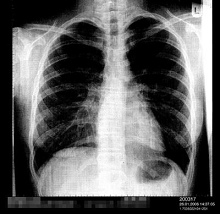

Hg-Dampf:

Atembeschwerden, Reizhusten, Schüttelfrost, Erbrechen,

verstärkter Speichelfluss, Metallgeschmack, Durchfälle,

Lungenentzündung, Lungenödem [Ansammlung von Flüssigkeit

in der Lunge, "Wasser in der Lunge"], Gelenkschmerzen;

Lungenentzündung (hier ein Röntgenfoto

einer einseitigen Lungenentzündung) wird durch

Quecksilbervergiftung durch Quecksilberdampf

begünstigt |